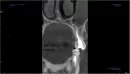

На КТ снимке просматривается затемнение левой верхнечелюстной пазухи, а также небольшой узкий тяж, идущий от четверки. Ранее проводилась операция по удалению кисты и резекции верхушки корня на двойке.

Может ли так просматриваться корень зуба и корень ли это? Насколько опасно наличие этого тяжа в пазухе?

По этому срезу диагностировать проблему невозможно. Обратитесь к хирургу на приём.